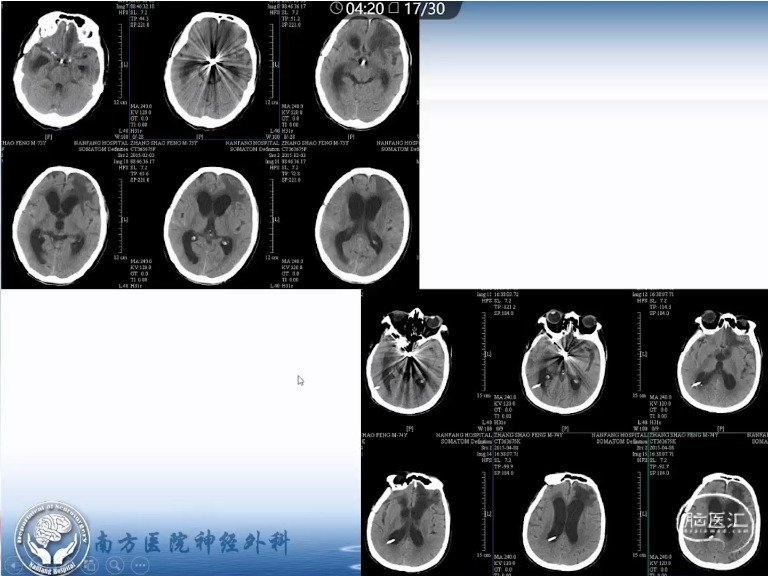

邱炳辉教授:重症aSAH ICP监测的时机

讲题重症aSAH ICP监测的时机